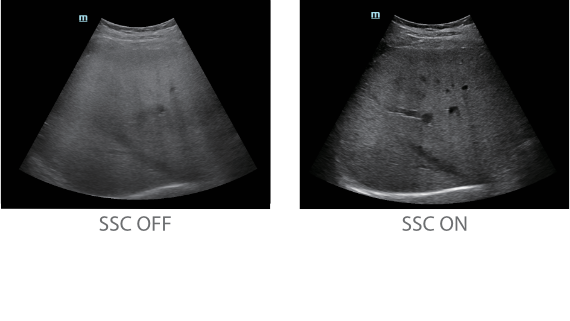

?? Resona 7? ???? ??? ?? ???? ??? ??? ???? ??? ?? ???? V Flow? ?? CNS ??? ?? 3D ??? ???? ?? ???? ?? ??? ?? ?? ?? ??? ??????. ???? ??? ??? ?? ?? ??? ??? ?? ?? ??? ??? Resona 7? ??? ???? ???? ??? ??? ??? ????.